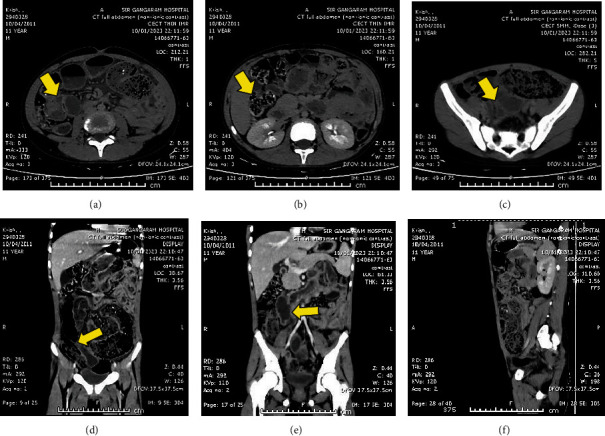

Background. Soil-transmitted helminth (STH) infections are a common global health issue that affects underprivileged communities without adequate access to clean drinking water, sanitation, and hygiene. Ascaris lumbricoides is the main species that infects humans. Among varied presentations, intestinal obstruction is common among children. Early detection of intestinal obstruction due to STH is critical to prevent severe complications. Here, we present the case of a 10-year-old child with acute intestinal obstruction due to roundworms. Case Report. A 10-year-old boy presented to the emergency department with recurrent abdominal pain, distention, and vomiting for three months with signs of peritonitis on examination. CT scan of the abdomen revealed roundworms in the distal ileum and a cocoon formed by adhesions of small bowel loops. Intraoperatively, worm balls were found in the proximal jejunum and ileum, causing small bowel obstruction, and a diseased segment of ileum had to be resected. The worms were removed, and an ileostomy was created. The patient was treated with albendazole and intravenous antibiotics such as ceftriaxone and metronidazole. An early closure of ileostomy was performed after 20 days. Histopathology showed roundworm eggs in the appendix and small bowel mucosa. Discussion. Ascaris lumbricoides infestation is a common cause of intestinal obstruction in children, and early detection is critical for avoiding severe complications. Prompt and appropriate treatment with antihelminthics and antibiotics is necessary to achieve a good outcome. In rare cases, surgical intervention may be required to treat intestinal obstruction caused by STH infections. In conclusion, the prevalence of STH infections highlights the need for public health interventions, such as improving access to clean water, sanitation, and hygiene, and for early detection and treatment to prevent severe complications such as intestinal obstruction.